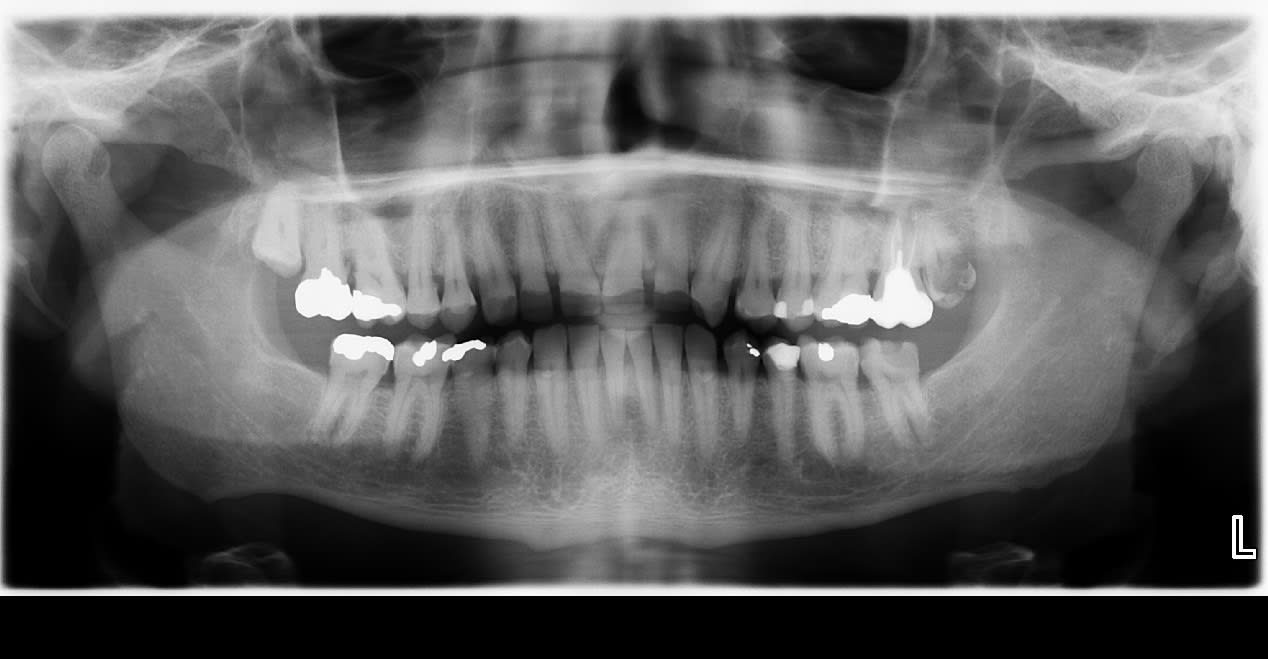

Tiens, j'en ai marre de ce cas, du coup je vous pose une colle sur celui de ce matin:

Sur la base de sa seule pano, saurez-vous trouver comment a fait ce sympathique monsieur pour bouffer jusqu'au trognon ses antérieures entre 14 et 24?

Récupéré quand 11 s'est fracturée à ras, mais il ne restait qu'une fine pellicule d'émail pour les autres.

Occlusion interferente ( croisée ? ) 45

Il ronge et mordille un truc très dur?

Natation a haute dose ?

Il ne serait pas en classe III avec articulé-croisé antérieur et l'usure concerne les faces vestibulaires ?

hummm pas sur , il a dit :

"Récupéré quand 11 s'est fracturée à ras, mais il ne restait qu'une fine pellicule d'émail pour les autres."

s il etait en articulé-croisé ant , il resterait la face palatine et les cingulum intacts costauds

et ça n expliquerait pas les diastèmes du haut .

Pas d'articulé croisé, ni la 45 ni aucune.

Pour PGC, je me suis effectivement demandé si sa pratique de la plongée n'avait pas accéléré l'histoire, mais (je ne crois pas qu') il s'agissait de la cause première.

Pour info, 5 6 7 ne sont presque pas usées, tout au plus des pentes cuspidiennes un peu plates. A l'inverse, de 14 à 24, c'est razibus.

Et le mr a comme il se doit des masseters de champion.

Pour la natation je sais pas, pour la plongée il mord sur le détendeur en caoutchouc.

:-))) "Sur la base de sa seule pano "

Effectivement , atm bien rondes , diastemes dents du haut ....tout concorde .